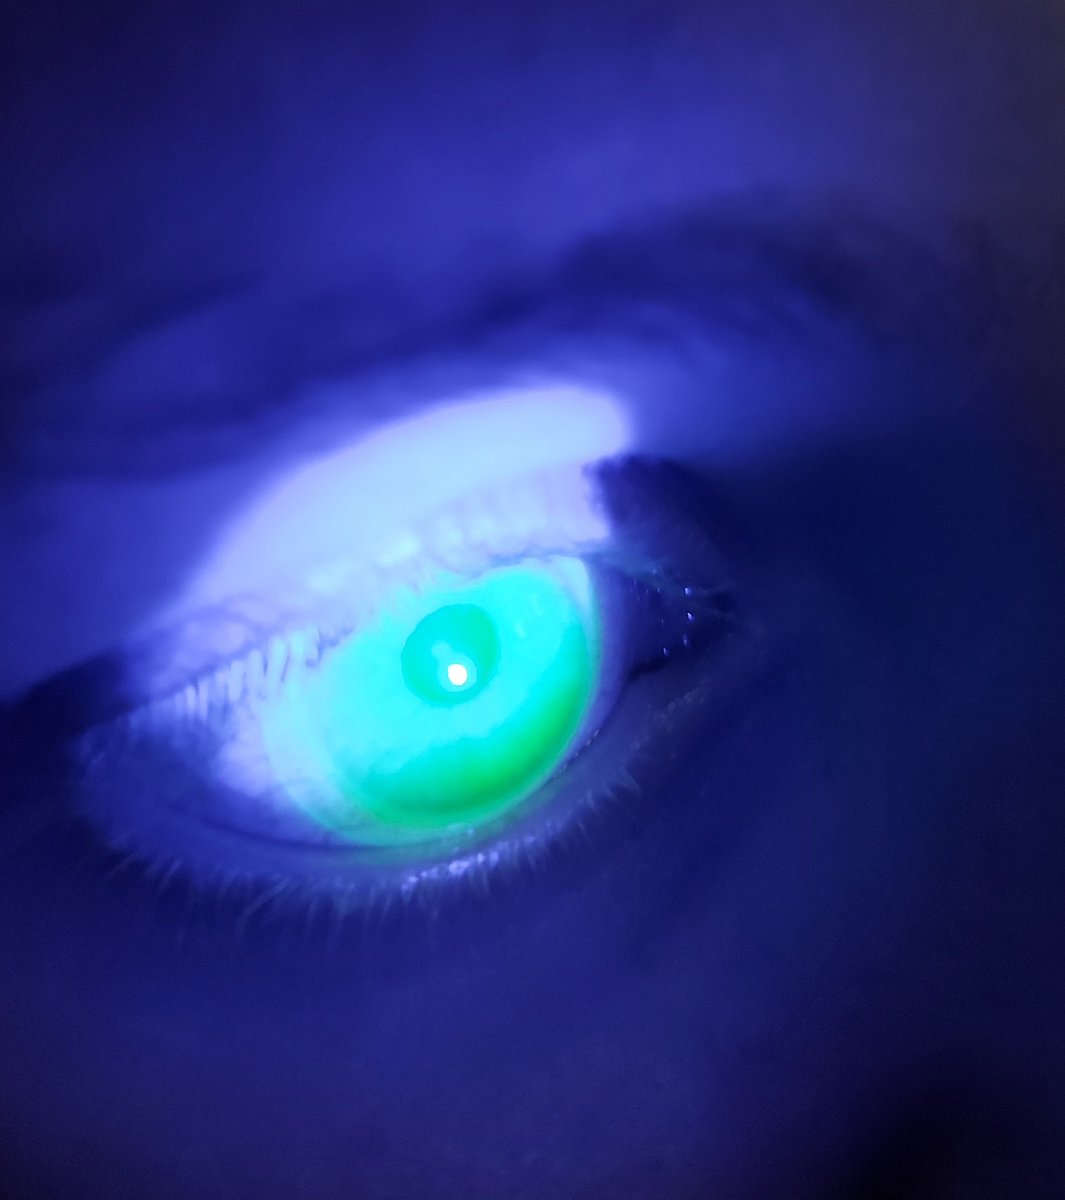

Last week our final year students @PlymOptometry had hands-on experience in fitting and assessing mini-scleral contact lens. Thanks to Ian Sexton from @CooperVisionUK in helping to run this workshop. #miniscleral #specialitycontactlens

mrj_vision's tweet image. Last week our final year students @PlymOptometry had hands-on experience in fitting and assessing mini-scleral contact lens. Thanks to Ian Sexton from @CooperVisionUK in helping to run this workshop. #miniscleral #specialitycontactlens

This week we had a session on mini-scleral lenses from @MeniconUK for our final year @PlymOptometry students. It was great to see their enthusiasm and skill to fit and assess the lenses. Thanks to Josie, James and Hans from @Meniconuk for running these sessions.

mrj_vision's tweet image. This week we had a session on mini-scleral lenses from @MeniconUK for our final year @PlymOptometry students. It was great to see their enthusiasm and skill to fit and assess the lenses.

Thanks to Josie, James and Hans from @Meniconuk for running these sessions.